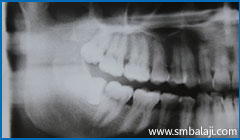

CASE I

X-ray showing two impacted lower canine teeth

X-ray taken before extraction of upper right third molar tooth